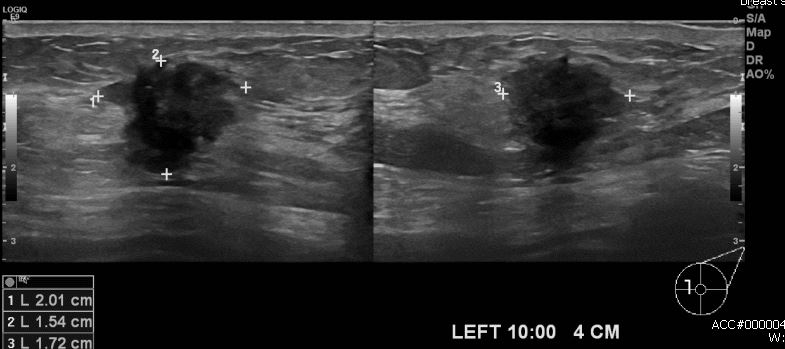

건강검진상 이상 소견으로 내원하신 80대 여성분으로 좌측 10방향에서 4cm 떨어진 거리의 혹 중앙핵생검 시행하여 좌측 침윤성 유관암 진단 되었습니다.